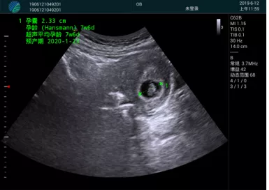

病例一:

清晰顯示孕囊,通過(guò)軟件包計(jì)算孕齡7w+6d

M20實(shí)時(shí)引導(dǎo),術(shù)中清晰顯示孕囊被破壞和抽吸針的過(guò)程,清晰顯示吸引針

抽吸結(jié)束后縱切子宮,孕囊已被完全抽吸,未見(jiàn)明顯殘留

橫切子宮,發(fā)現(xiàn)右側(cè)宮腔靠近宮角處有少許脫模樣殘留

M20引導(dǎo)下,抽吸針找到右側(cè)宮角處再次清掃

二次抽吸后再次進(jìn)行超聲檢查,宮腔未見(jiàn)殘留,宮腔線(xiàn)清晰顯示

超聲引導(dǎo)下可視化人流是技術(shù)安全性的保障,一般對(duì)人流術(shù)設(shè)備預(yù)算不高,M20具備婦產(chǎn)科軟件包,且穿透力圖像質(zhì)量好,既滿(mǎn)足人流引導(dǎo)需要,也可用于床旁超聲的需求。